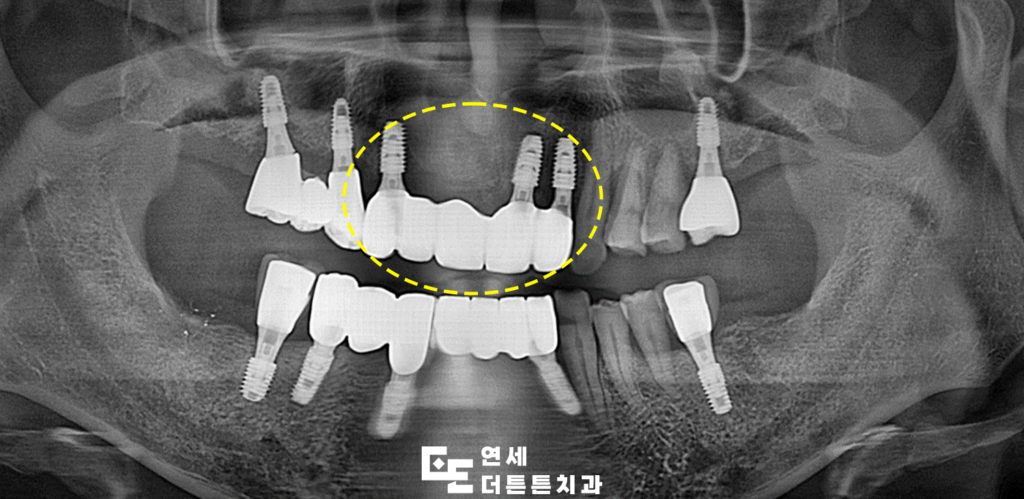

최종 보철물까지 완성한 모습입니다.

최근에는 수락산역치과에서 임플란트를 할 때

디지털 CT, 3D 스캐너 등 장비를 활용해

치조골 상태와 잇몸 라인, 교합 상태까지

정밀 분석하고 컴퓨터 시뮬레이션을 통한

맞춤 식립이 가능해졌는데요.

이를 통해 통증과 출혈을 줄이면서도

환자에게 더욱 자연스러운 결과를

제공할 수 있습니다.